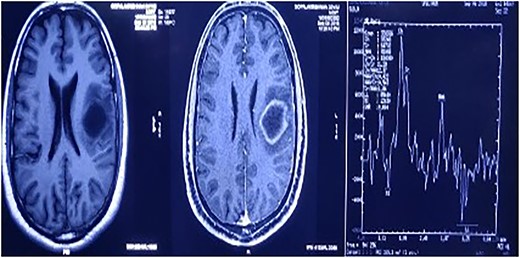

A magnetic resonance spectroscopy (MRS) was performed and revealed an increased choline, considered as a marker of neoplasms, reduced NAA, and prominent lipid/lactate peaks. (Ch/NAA-4.0) (Ch/Cr-1.7) (Fig. 2).

MRS showed an increased choline, reduced NAA, and prominent lipid/lactate peaks; (Ch/NAA-4.0) (Ch/Cr-1.7).